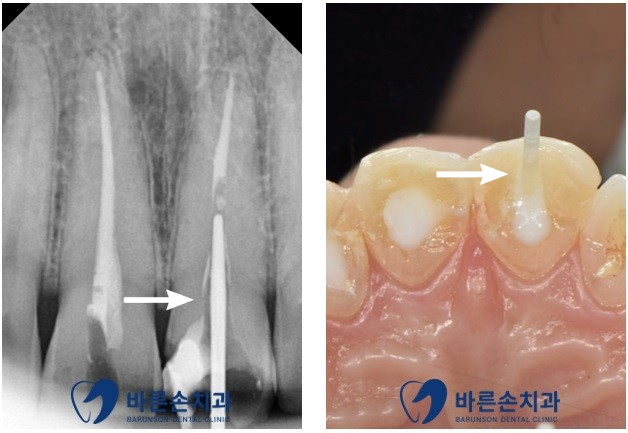

정확한 손상 정도를 확인 하기 위해 엑스레이 촬영을 합니다

엑스레이 확인 결과 육안상으로 보는 것 보다

파절정도와 범위가 크고 이로인해 치아의 신경이 노출된 것을 알 수 있었습니다

치아의 신경관 내 포스트를 적합 후 치아의 파절 부위를 보강해 주고

크라운 제작을 시행 합니다